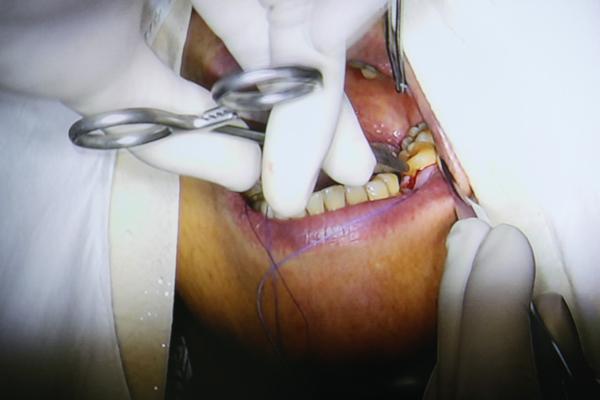

手术现场直播

今天参与手术直播的是一位67岁的郑阿姨,手术医生冯医生为郑阿姨种植的是左下第6颗牙齿。在手术开始前,专家对郑阿姨的牙齿情况进行了会诊。

种好后对种植部位进行缝合